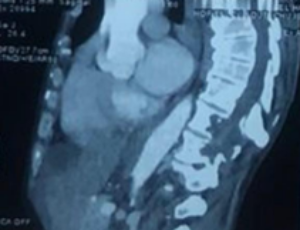

AbstractAbstract Hydatidosis is an anthropozoonosis caused by the development of cysts corresponding to the larval form of a taenia called Ecchinococcus granulosis. Bone hydatidosis is rare, accounting for only 0.9% to 2.5% of all cases. We report the case o.....